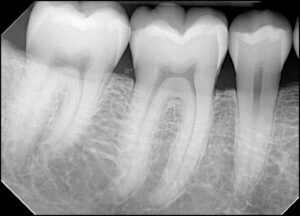

Рентгеновский взгляд: зачем нужен прицельный снимок зуба

В современной стоматологии диагностика играет ключевую роль в успешном лечении. Одним из важнейших инструментов в арсенале стоматолога является рентгенография, а в частности – прицельный снимок зуба. Эта процедура позволяет получить детальное изображение конкретного зуба и окружающих его тканей, что необходимо для точной постановки диагноза и планирования лечения. Своевременная диагностика – залог здоровья вашей улыбки. Если …